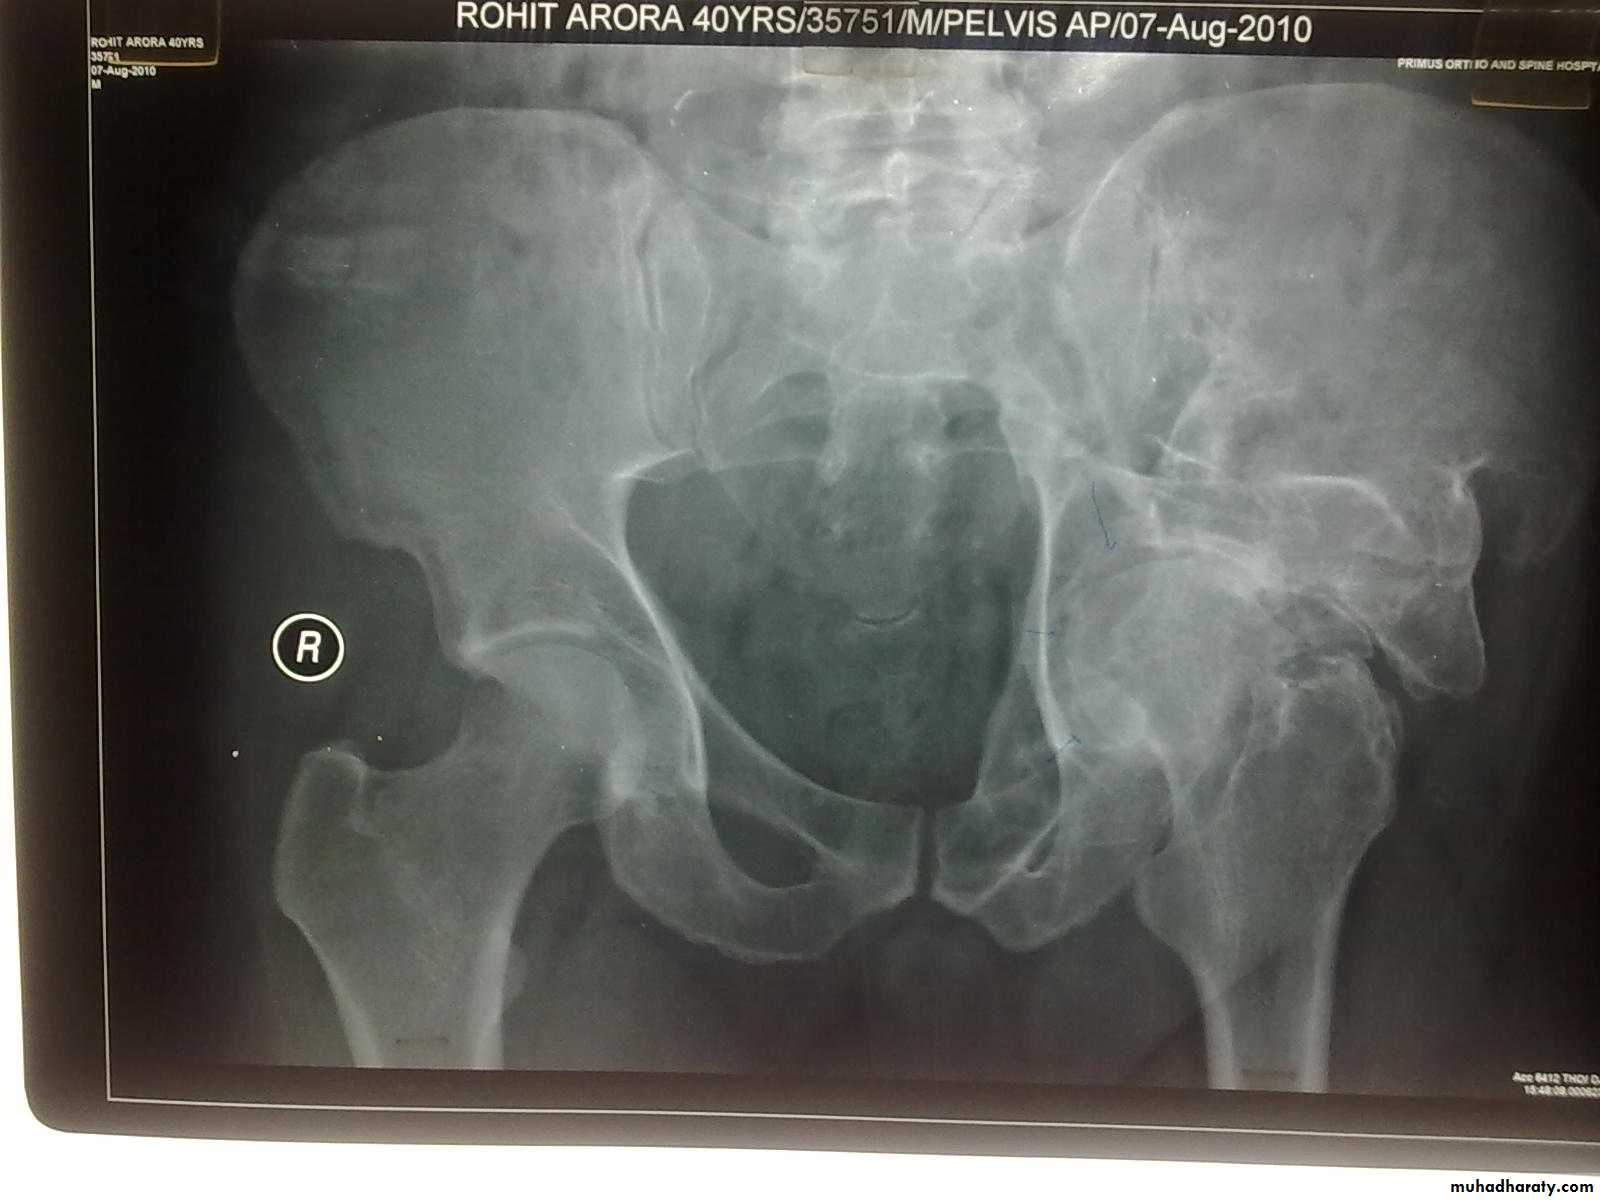

The golden role is to x ray the pelvis in every case of sever injure

and with femoral fracture to include both the hip and knee.

Radiological examinations

X-R AP view we can see the dislocation with or without associated fracture posterior wall of the acetabulum,

or fracture head of the femur,

And neck of femur.

Lower limbs